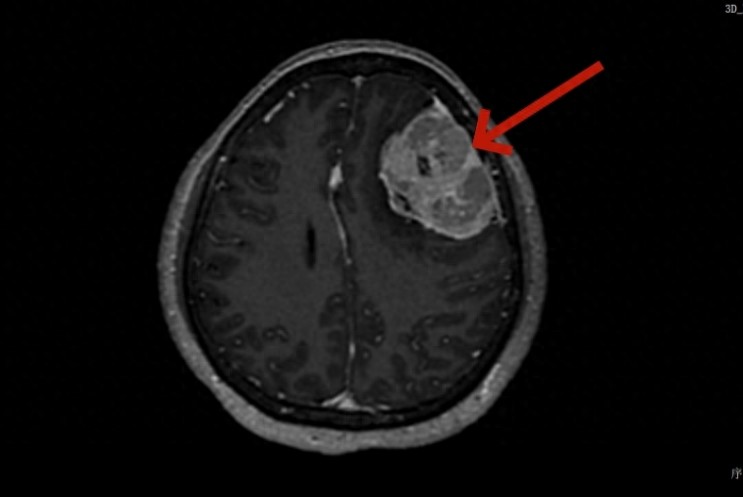

检查结果清晰地揭示了病灶的全貌:一个直径达6厘米的巨大肿瘤,位于掌控着身体感觉和部分运动功能的右侧顶部,更棘手的是,肿瘤已经侵犯了大脑中央最重要的血液回流通道——矢状窦。这无疑大大增加了手术的难度和风险。